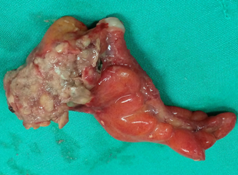

Total Hysterectomy specimen .Both ovaries occupied by the signet cell gallbladder carcinoma (Courtesy Dr. V. Penopoulos)